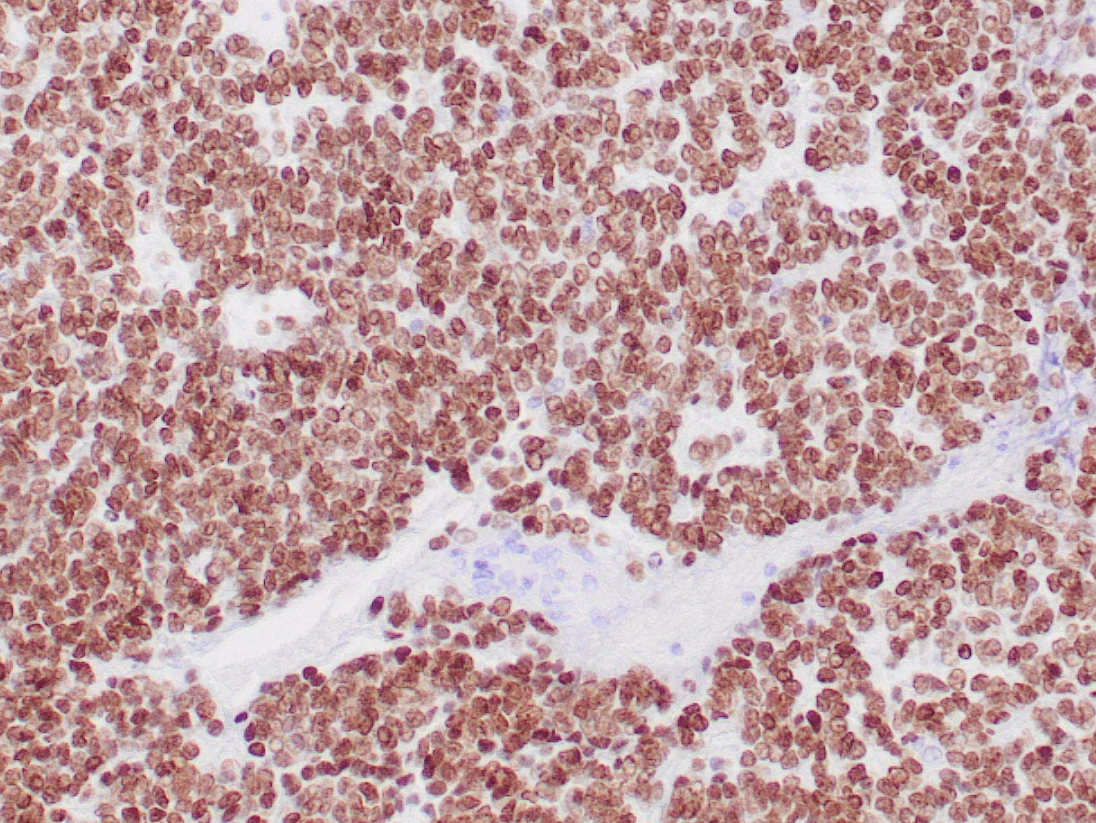

NAPSIN A (ZR206)